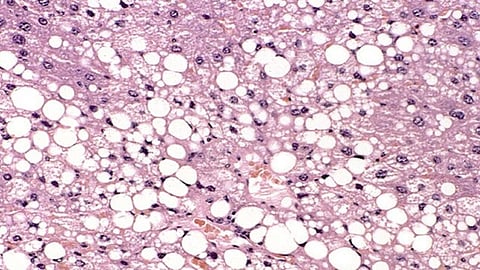

Diagnosing a fatty liver involves a combination of medical history assessment, physical examination, blood tests, imaging tests, and, in some cases, liver biopsy.

6. A liver biopsy is recommended to confirm the biopsy and assess the extent of liver damage. (2)